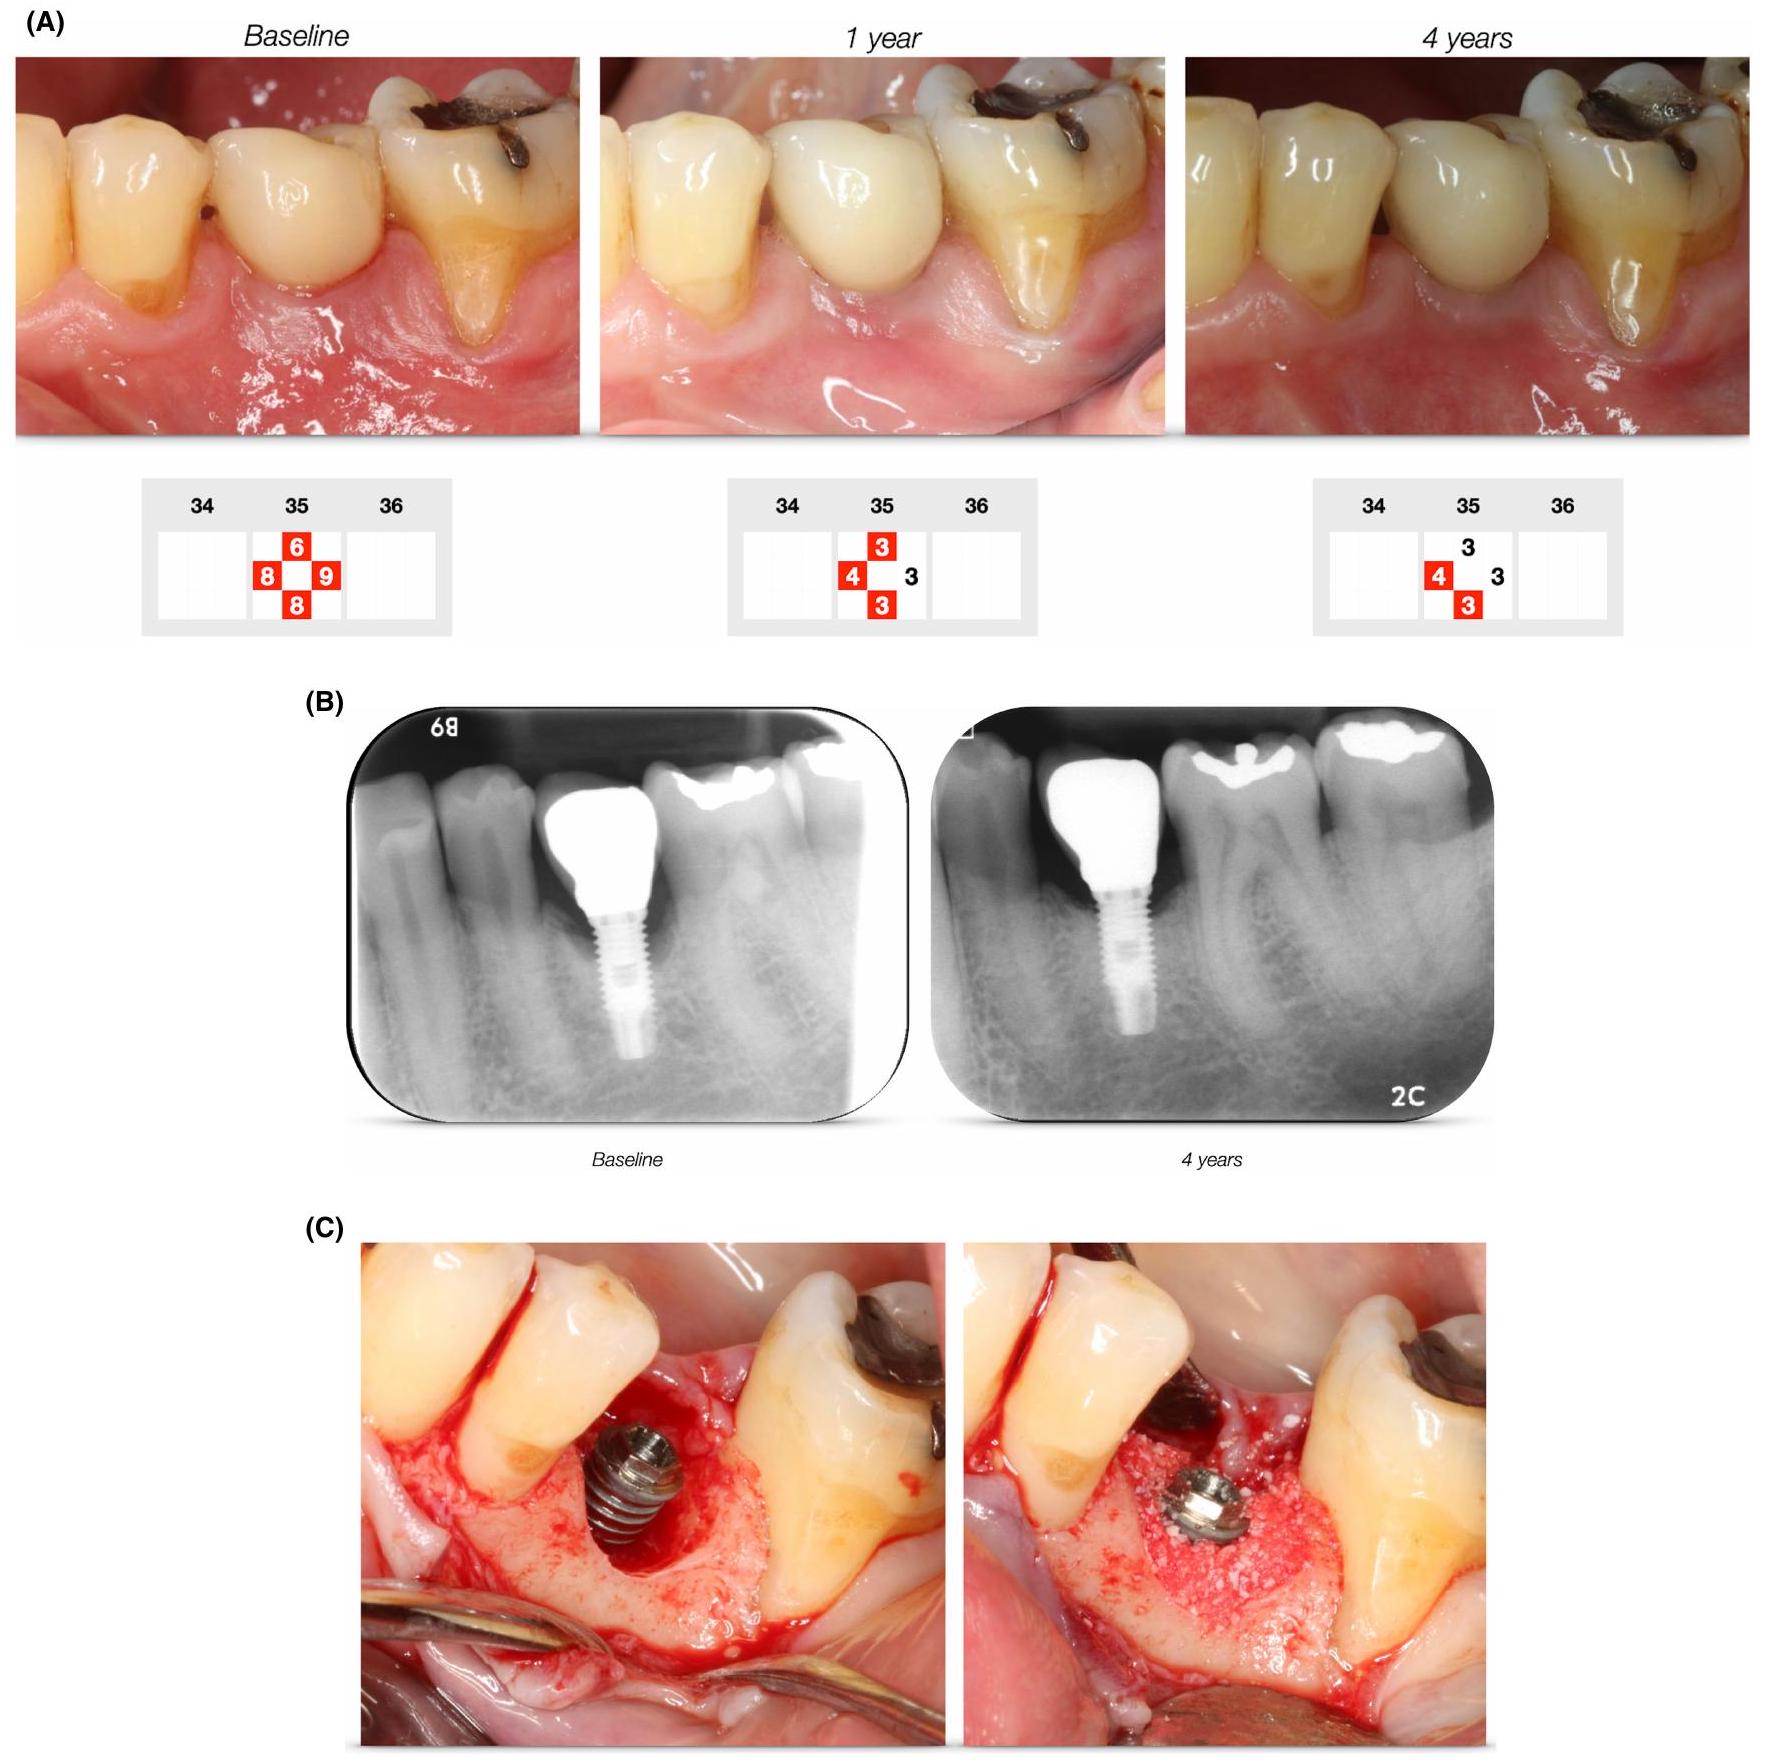

In the section on methods, the research examines the efficacy of various reconstructive techniques in treating peri-implantitis, aligning with existing periodontal literature. These techniques involve the application of bone replacement grafts, membranes, and bioactive agents to address bony defects resulting from disease. The primary goals of these methods include the regeneration of bony defects, re-osseointegration, and preservation of soft tissue height. Most studies reviewed are European, with many comparing reconstructive methods to access flap surgery, which serves as a control.

Despite the extensive evaluation of these techniques, systematic reviews indicate that reconstructive methods do not significantly improve primary outcomes such as probing pocket depth and bleeding on probing. For instance, a multicenter randomized controlled trial by Jepsen et al. found minimal differences in probing depth reduction between the control and test groups after 12 months. Similarly, other studies, including those by Renvert et al. and Derks et al., reported comparable outcomes between groups with and without reconstructive interventions. However, some studies noted improvements in radiographic parameters, suggesting potential benefits in bone level gain, although the clinical significance of these findings remains uncertain. Additionally, the impact of reconstructive measures on soft tissue levels has been infrequently assessed, with some evidence indicating less recession in test groups compared to controls.